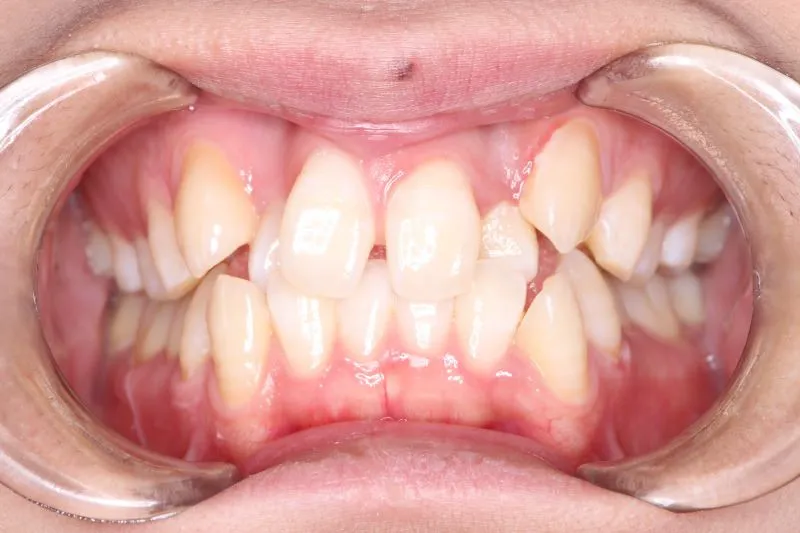

【大人の矯正】叢生・八重歯・交叉咬合・非抜歯症例・19歳女性【R.T様】

初診時年齢 19~29歳 (女性) 主訴 ガタガタ・交叉咬合が気になる

診断名 叢生・交叉咬合 装置名

ガタガタ・八重歯を主訴に来院された患者様です。

頬杖をする癖がおありでした。

初診